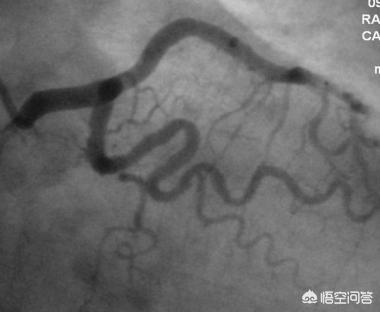

Le cœur de la maladie coronarienne est l'ischémie et l'hypoxie des cardiomyocytes, et la cause la plus fréquente de l'ischémie et de l'hypoxie des cardiomyocytes est la sténose de l'artère coronaire due à l'athérosclérose coronarienne. Le diagnostic de la maladie coronarienne repose généralement sur une méthode simple de diagnostic clinique : en cas de douleur précordiale liée à l'activité, de la taille de la paume de la main, pouvant être soulagée après un repos de quelques minutes à dix minutes, en particulier en cas d'hypertension, d'hyperlipidémie, de diabète sucré et d'autres facteurs de risque cardiovasculaire du patient, le diagnostic de la maladie coronarienne peut être directement établi par le diagnostic clinique. Pour le diagnostic final de la maladie coronarienne, la méthode la plus classique consiste à s'appuyer sur les résultats de l'angiographie coronarienne ou de la CTA. Si le degré de sténose des artères coronaires atteint 50 % ou plus, le diagnostic de la maladie coronarienne peut être confirmé.

Avec le développement d'autres nouvelles technologies telles que l'échographie intravasculaire, de meilleures méthodes d'examen ayant moins d'impact sur le corps humain apparaîtront certainement à l'avenir, mais jusqu'à présent, le diagnostic et la gestion des maladies coronariennes reposent encore principalement sur l'angiographie coronarienne.

L'étalon-or est la coronarographie avec rehaussement coronarien pour le dépistage.